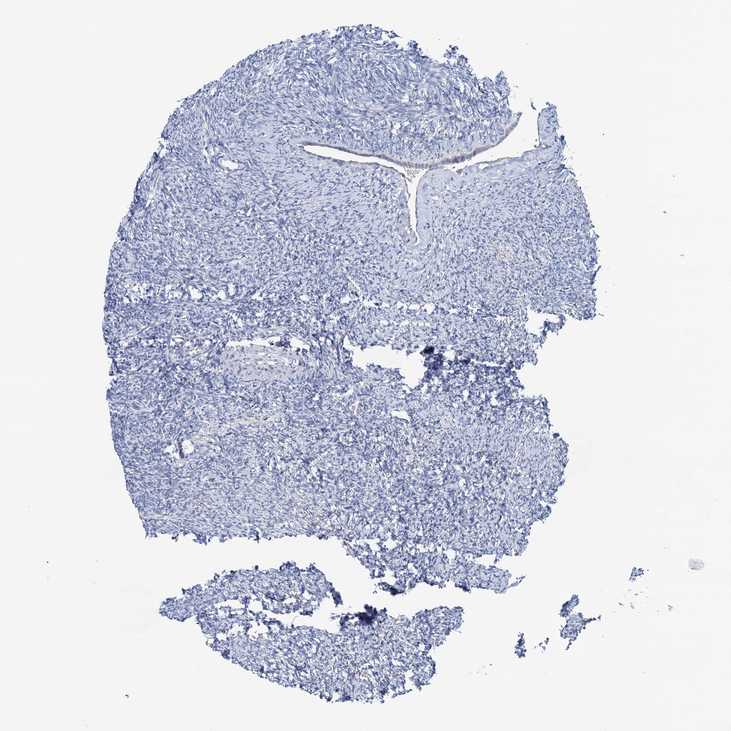

OLFML1